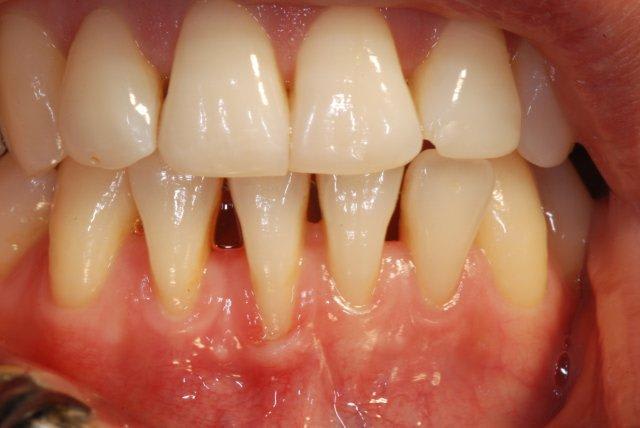

Bon j'ai trouvé !

Greffon unique

conjonctif enfoui pour la 44

Épithélio-conjontif pour la 43

Pas facile le prélèvement, à la simple lame 15

Portion conjontif avec approche par volet, pour refermer la plaie au palais, l'autre portion pleine épaisseur.

Sutures en 3 étapes

a) Gut 5-0 pour stabilisé le greffon

b) Vicryl 4-0 pour le point en "X" au périoste sur la 43

c) Poly 6-0 pour refermer le tout

La maturation de la plaie d'ici 2 mois devrait donner quelques chose de bien.

Si le frein tire trop, je sortirai le laser...

Contrôle à 6 mois

Je retourne sur la 43 ou je laisse ?